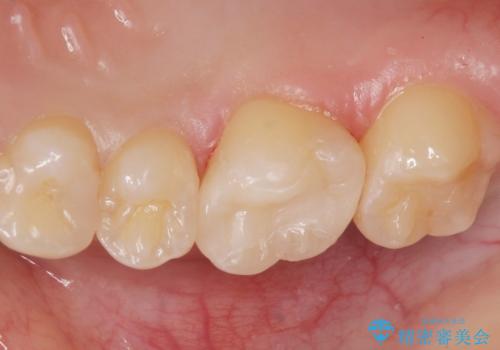

コンタクトカリエスの治療。(e-maxインレー)

- 歯が染みるとの事で来院。歯と歯の間にカリエス(虫歯)が出来ていて穴が空いていました。

拡大鏡下で虫歯を全て取り除き、e-maxインレーで治療を行いました。

適合の良い詰め物が入りました。

歯と歯の間の虫歯は歯ブラシでは予防しずらく、フロスを毎日行わないと虫歯になります。